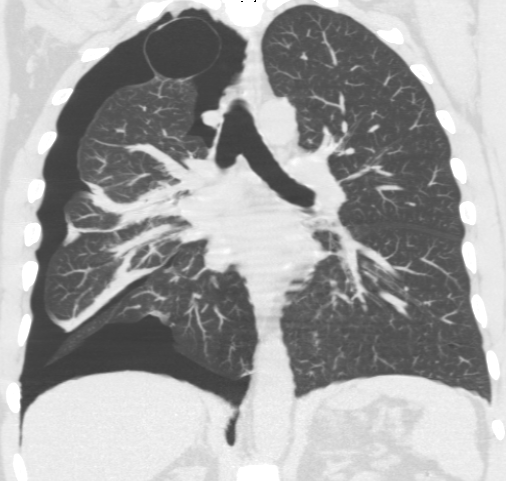

Pneumothorax

Pneumothorax is air buildup in the pleural space.

Pneumothorax leads to collapse of a portion of the lung.